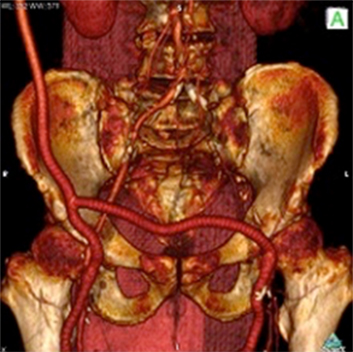

<手術前>両側総腸骨動脈(お腹の中にある足のつけねの動脈)と両側大腿動脈(太ももの動脈)に閉塞、狭窄部位があり、運動障害(間歇性跛行)や皮膚障害(壊死)を引き起こし、車椅子に乗られての入院となりました。

<手術後>右の鎖骨下~腋窩動脈(鎖骨の下から脇の下にかけての動脈)から両側大腿動脈、さらにそこから両側膝窩動脈(膝の裏の動脈)にバイパス手術を施行しました。

運動障害、皮膚障害も改善し、歩いて退院されました。

両側総腸骨動脈狭窄、閉塞

両側大腿動脈狭窄、閉塞